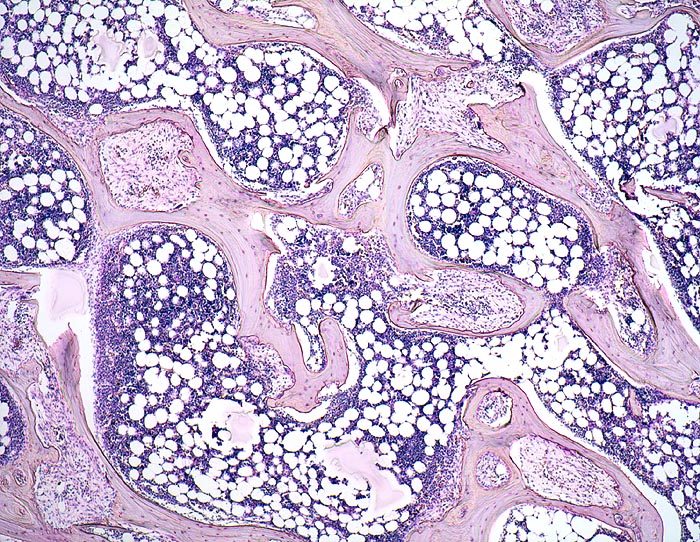

Histologisch findet sich beim Hyperparathyreoidismus eine gesteigerte Osteoklastentätigkeit mit Tunnellierung der Knochenbälkchen und gleichzeitig eine gesteigerte Knochenneubildung mit Fibrose der peritrabekulären Markräume. Die Maximalvariante eines sogenannten „Braunen Tumors“ -Osteodystrophia fibrosa generalisata cystica von Recklinghausen- kommt heute in Mitteleuropa praktisch nicht mehr vor. Die braune Farbe dieses Tumors wird durch sekundäre Einblutungen und Siderinablagerungen verursacht.

• Dünne Spongiosabälkchen mit herdförmiger peritrabekulärer Fibrose.

• Vermehrte Osteoklastentätigkeit: Spongiosabälkchen mit tiefen Resorptionslakunen, welche die Bälkchen z.T. tunnelartig aushöhlen.